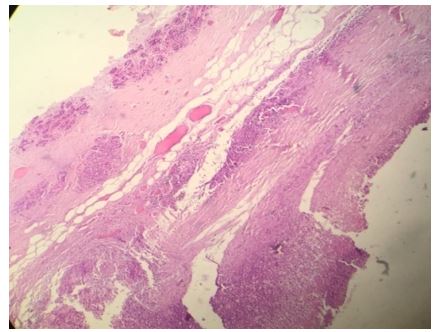

She had pre-operative ultrasound scan of the breast which showed a round hypo-echoic lesion (see figure 2). Histopathology examination of the excised specimen showed a cyst that contained folds of laminated chitinous layer which was partly lining the wall of the cyst and the encompassing areas did show chronic inflammation with sheets of foamy macrophages (see figures 3 and 4). The microscopic examination of the specimen also showed foreign body giant cell reaction as well as occasional ill-formed granuloma and the surrounding normal breast tissue was also visualised (see figures 5 and 6). She was sent for further treatment.